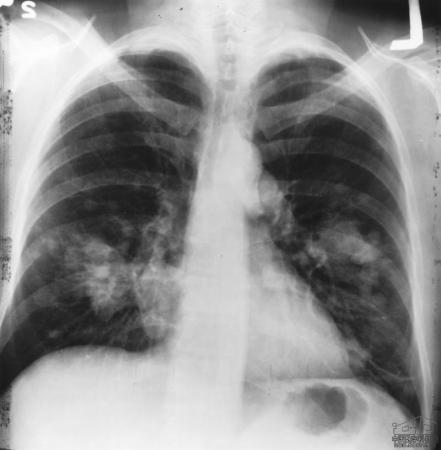

Using a new technique called whole-genome profiling, MIT scientists have now pinpointed a gene that appears to drive progression of small cell lung cancer, an aggressive form of lung cancer accounting for about 15 percent of lung cancer cases.

Small cell lung cancer kills about 95 percent of patients within five years of diagnosis; scientists do not yet have a good understanding of which genes control it. Dooley and her colleagues studied the disease's progression using a strain of mice, developed in the laboratory of Anton Berns at the Netherlands Cancer Institute, that deletes two key tumor-suppressor genes, p53 and Rb.